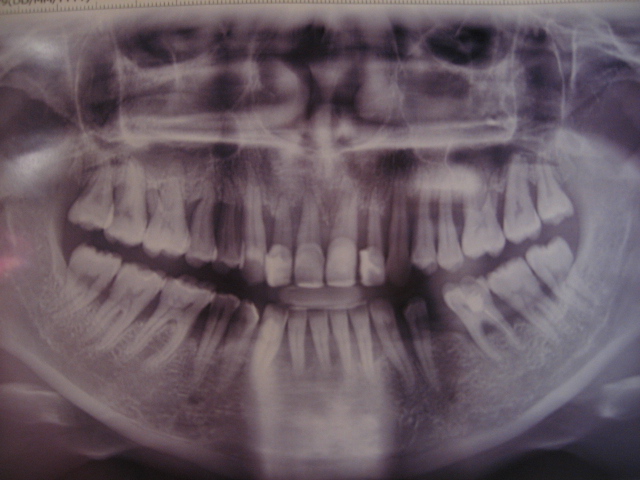

Здравствуйте! Ув. стоматологи, что же делать, как же быть?

Нажмите на изображение для увеличения

Название: IMG_9362.JPG

Просмотров: 27

Размер:	130.8 Кб

ID:	8446875Нажмите на изображение для увеличения

Название: IMG_9363.JPG

Просмотров: 24

Размер:	132.1 Кб

ID:	8446876

Цитата Сообщение от kisskiss Посмотреть сообщение

возраст?

наличие сопутствующих заболеваний?!